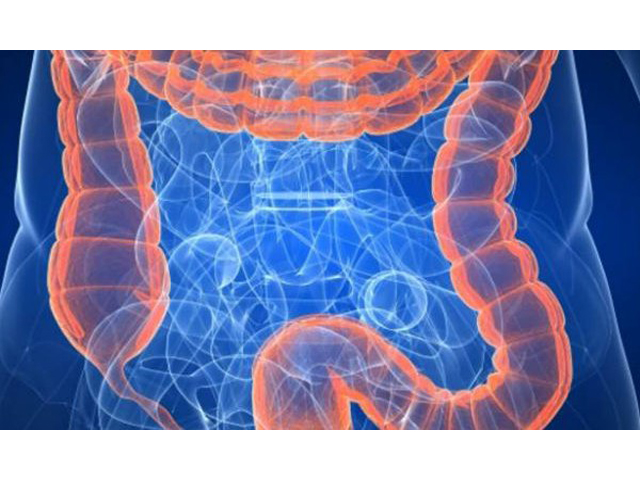

Znate li koji su simptomi raka debelog crijeva?

Rak debelog crijeva predstavlja drugi najčešći uzrok smrtnosti od malignih bolesti u našoj zemlji. Kod muškaraca je odmah iza raka pluća, a kod žena iza raka dojke.

Rak debelog crijeva drugi je po redu vodeći uzrok smrti zbog malignih bolesti u razvijenim zemljama, a četvrti diljem svijeta, tvrde stručnjaci, unatoč činjenici što se ova bolest može izliječiti kirurškom intervencijom ako je dijagnoza postavljena u ranijoj fazi. Trenutne terapije za ovu malignu bolest uključuju operaciju, kemoterapiju, biološku terapiju i zračenje, piše Ordinacija.